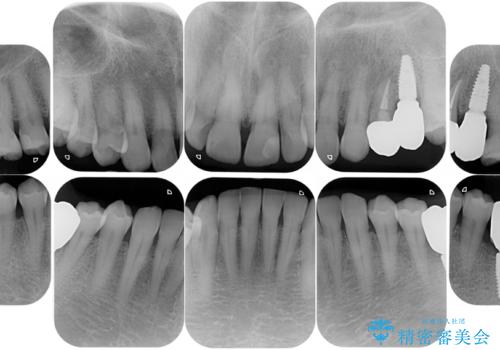

- リタイアを期に海外に移住されることになり、出発前に全顎的に治療をしておきたいと来院された患者様です。最短期間で治療を終了できるよう、事前に綿密な計画を立てたうえで集中的に治療を行いました。

期日が決まっていたため、それぞれの処置にかかる日数・時間を綿密に計算したうえで短期間での集中治療を行いました。毎回の処置時間を長めに設定し、1回の来院でより多くの処置を行えるようにしたおかげで全顎的な治療も短期間で仕上げることができました。